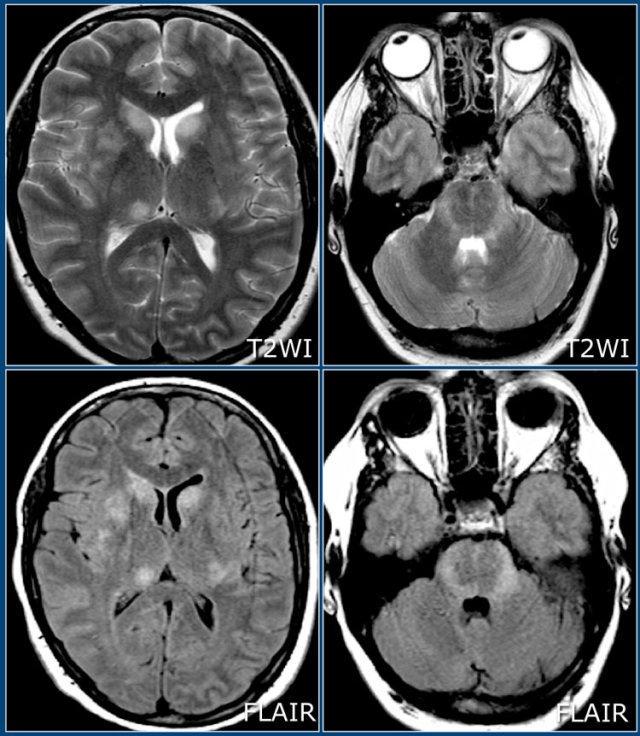

Typical findings for MS as seen in this case are:

- Ovoid lesions perpendicular to the ventricles (Dawson fingers).

- Enhancing lesion.

- Multiple lesions adjacent to the ventricles.

Dawson fingers are typical for MS.

They represent areas of demyelination along the small cerebral veins that run perpendicular to the ventricles.

If needed this can be demonstrated using SWI

The enhancement will be present for about one month after the occurrence of a lesion.